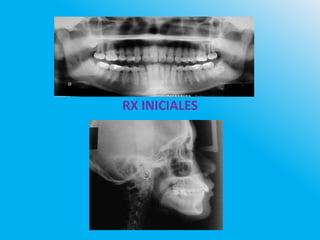

RX INICIALES